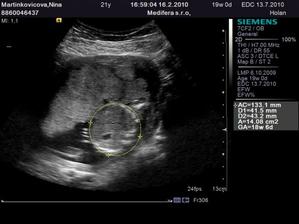

♥ 16.2. (utorok) ideme na 4D ultrazvuk!! 🙂 - Boli sme, nádherný zážitok!!! Je to chlapec ako sa patrí, úplne zdravý a krásny!!! 🙂 4D nám lekár ukázal len nožičky a pipíka, lebo tvárička nie je dobre vidieť tak skoro, ale to vôbec nevadí... 🙂

♥ 19.4. (pondelok) ultrazvuk - malý má už 1,2 kg, je nádherný!! 🙂